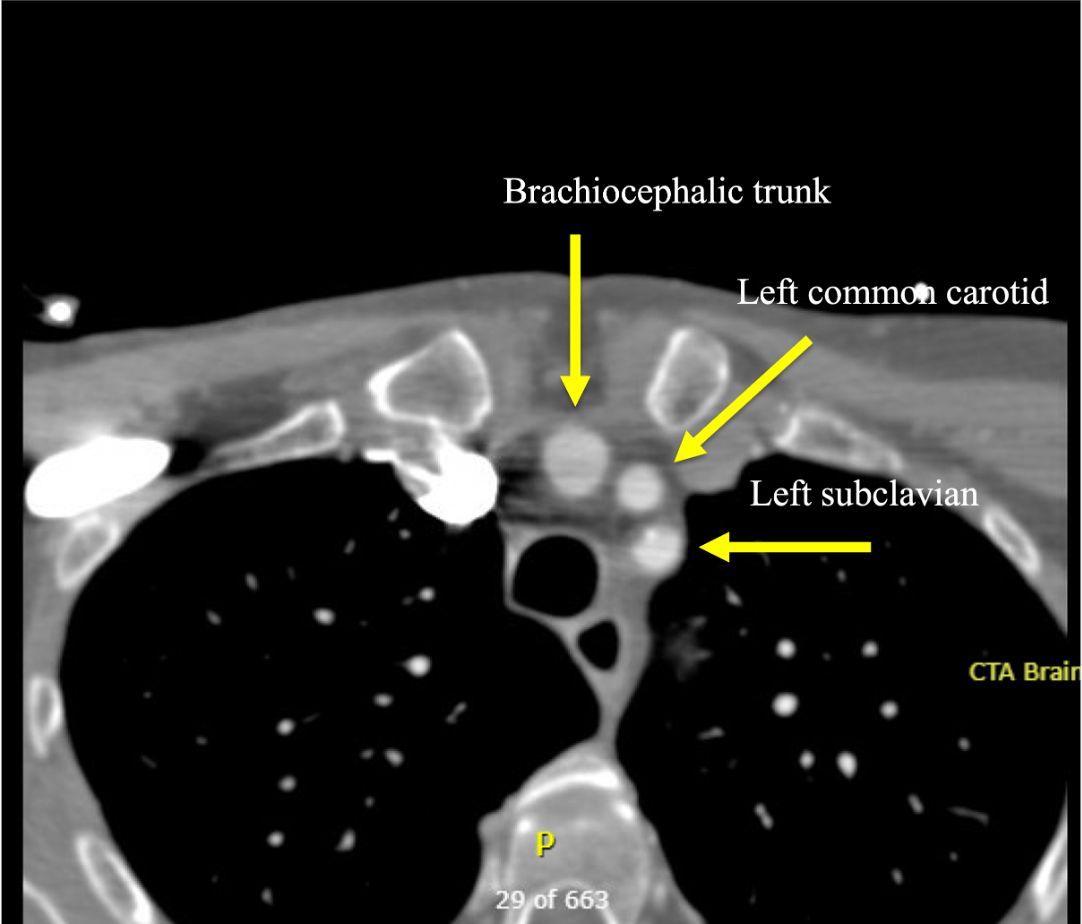

Name the three major branches off the aortic arch, as seen on this axial CTA: